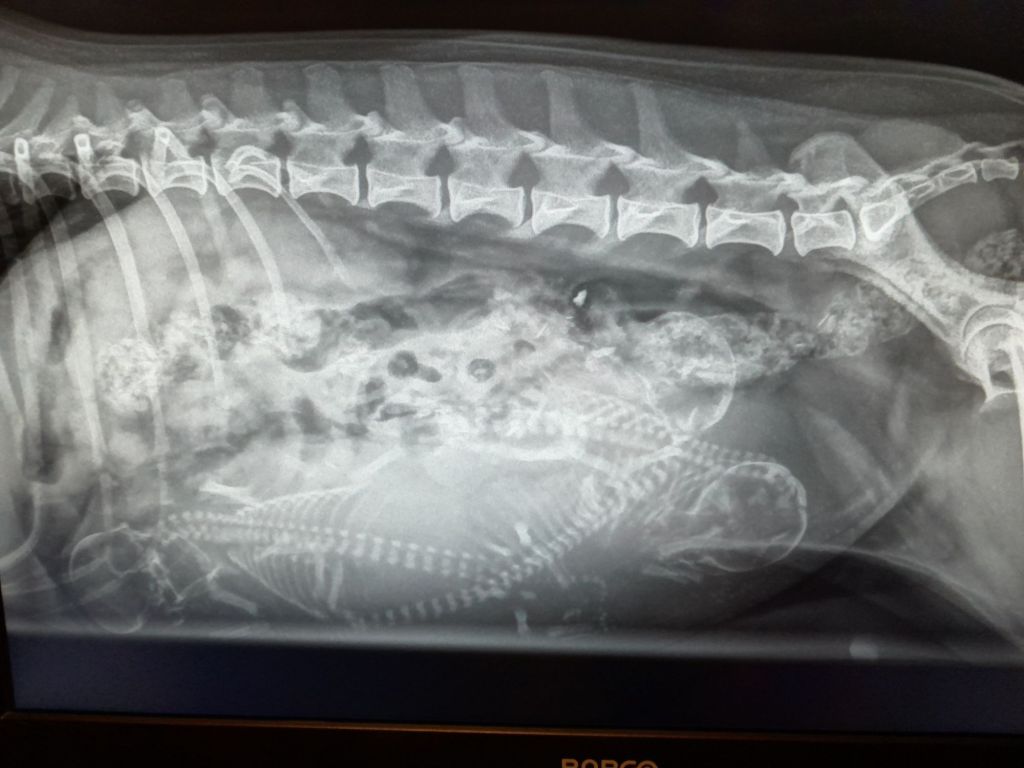

Idag har vi varit till Alandia Veterinärklinik för att dubbelkolla hur många valpar det är som gömmer sig där inne. Vid ultraljudet hittade vi 3st och röntgen kunde idag bekräfta att det är tre små gynnare som gömmer sig där inne. Jag hade önskat en eller två valpar till, men jag är ändå oerhört glad över de tre små som finns där inne. Tre är kanske en ganska lagom kull att orka med när det är första gången för Ronja, och även för mig som uppfödare. Jag har varit med och förlöst en valpkull tidigare, men det är jättemånga år sedan när min första hund föddes, det är en fin upplevelse. Jag har tidigare fött upp några föl hemma på gården, och i mina unga år som djurskötare har jag hjälpt en och annan kalv till världen.

Hittar ni de tre små valparna?